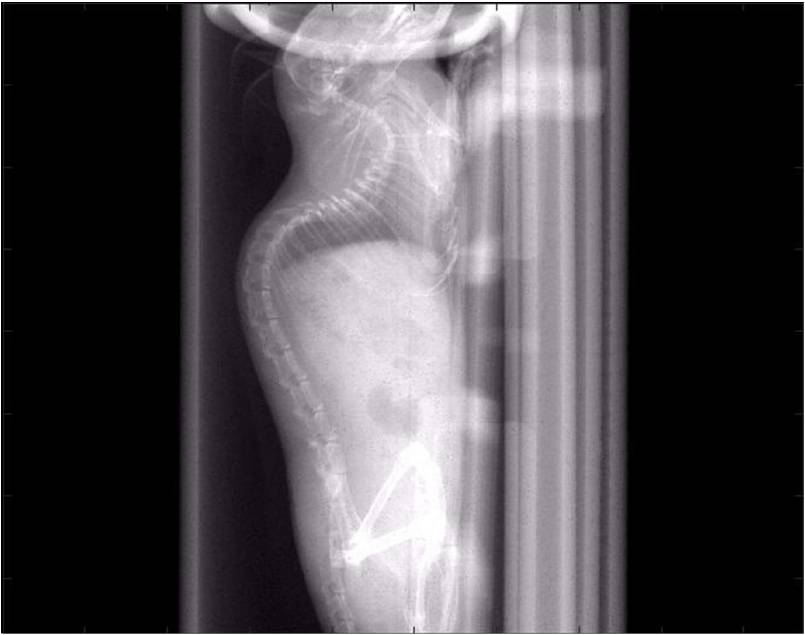

檢測案例

腫瘤血管生成

肺轉移

小鼠模式,22.5μm像素

正常

8天 14天

無造影劑注入 造影劑注入